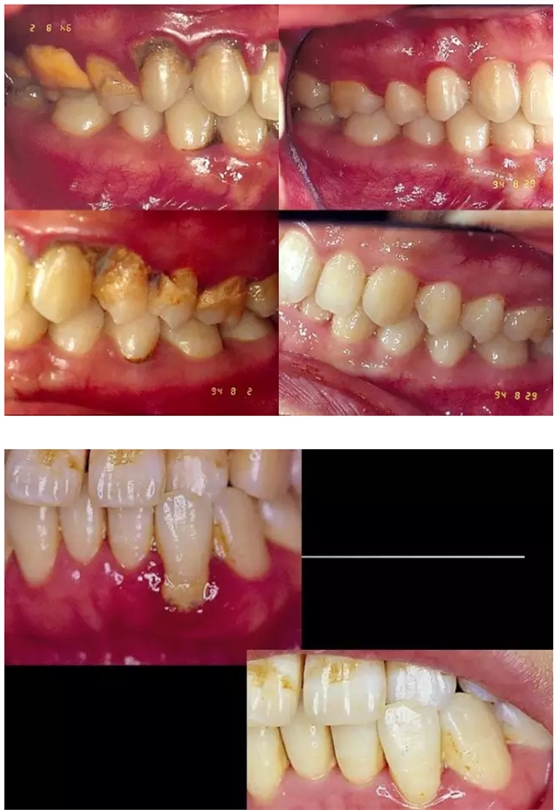

61.png

63.png

64.png

65.png